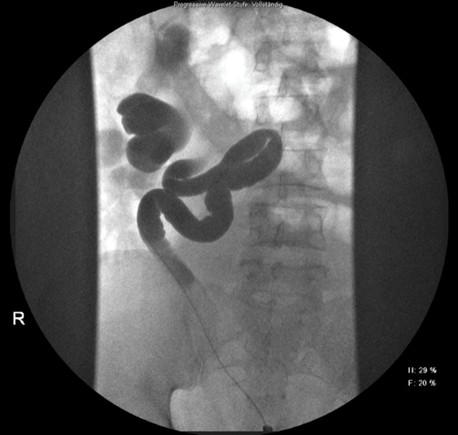

Therapeutisch erfolgte eine Urethrozystoskopie, retrograde Uretropyelographien mit Single-J-Anlagen bds. (links nach Freiresektion des Ostiums (TURB). (Abbildung 1 [Abb. 1] & Abbildung 2 [Abb. 2]). Eine offen-chirurgische Liporesektion blieb ohne operativen Erfolg, sodass bei fortbestehenden Ektasien eine Kontroll-Szintigraphie eine abnehmende Gesamtclearance (links: 66%, rechts: 34%) zeigte.